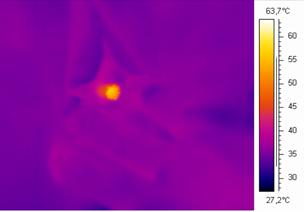

インティマレーザー(Vタイトニング)は、従来のレーザーでは表面に限局されていた効果を、Fotona社独自のSMOOTH MODE(スムースモード)※技術により粘膜表面へのダメージを最小限にし、その粘膜下層に60℃~63℃の熱だまりを作ります。

この温熱効果により奥深くから膣の引締め、細胞の再構築を行うことが可能になりました。※SMOOTH MODEスムースモード:250msの超ロングパルスのエルビウムヤグレーザー

インティマレーザーの設定温度

インティマレーザーは温度調整の幅がとても広く、その方の膣の状態により照射する温度が異なってきます。

弱すぎれば効果が感じられない場合もありますが、強すぎると膣内が硬くなってしまうリスクもあります。

オートマティックで照射するマシンも出ていますが、当院ではあえてマニュアル照射を採用し、状態に応じてお一人ずつ温度設定を変えています。

インティマレーザーの照射時間

インティマレーザーを照射することで膣内の温度は上昇していきます。

当院では照射するごとに膣内の温度と血流を確認しながら最適な状態を目指します。